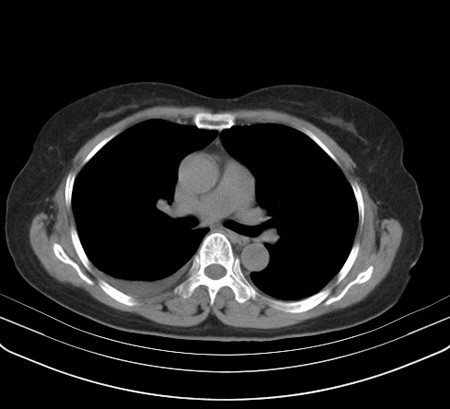

以下是引用余辉在2009-2-19 20:10:00的发言:[br]多考虑急性感染性病变,右中叶尚可见多枚小斑片状影,多为化脓性肺炎,双侧胸腔积液

以下是引用随光逐影在2009-2-19 20:33:00的发言:[br]1)考虑右肺炎症;建议抗炎治疗后复查。2)双侧胸腔积液(以右侧为甚)。

以下是引用花凤凰在2009-2-19 20:46:00的发言:[br]病人有发热,胸痛急性起病,主要病变位于右肺中叶外侧段,呈楔行改变,位于外带胸膜下,考虑为肺梗塞可能!!!!!!!!!!!!!!!!!!!!!!!!!!!!!!!!!!!